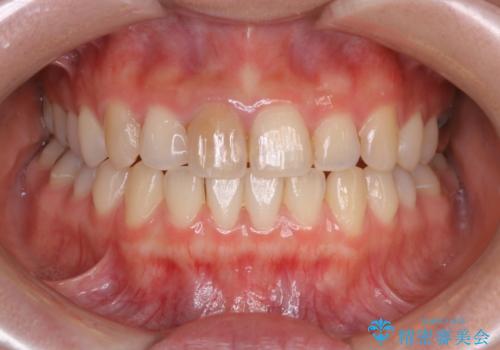

- 前歯一本だけ色が暗いことが気になりご相談にいらした患者様です。周辺の歯と色味をぴったり合わせることで自然な仕上がりになりました。

根管治療をした歯は神経のある歯と比較して強度が下がり、長期的に破折のリスクが高まると言われています。破折のリスクを軽減させるため、根管治療を行った歯に対しては歯冠をすべて覆うクラウンという被せ物にて補綴処置を行います。

自費診療で用いられる材料は保険適応の材料に比べて、より精密で適合の良い被せ物作ることができるため、長期的な虫歯のリスクを大幅に減らすことが可能です。